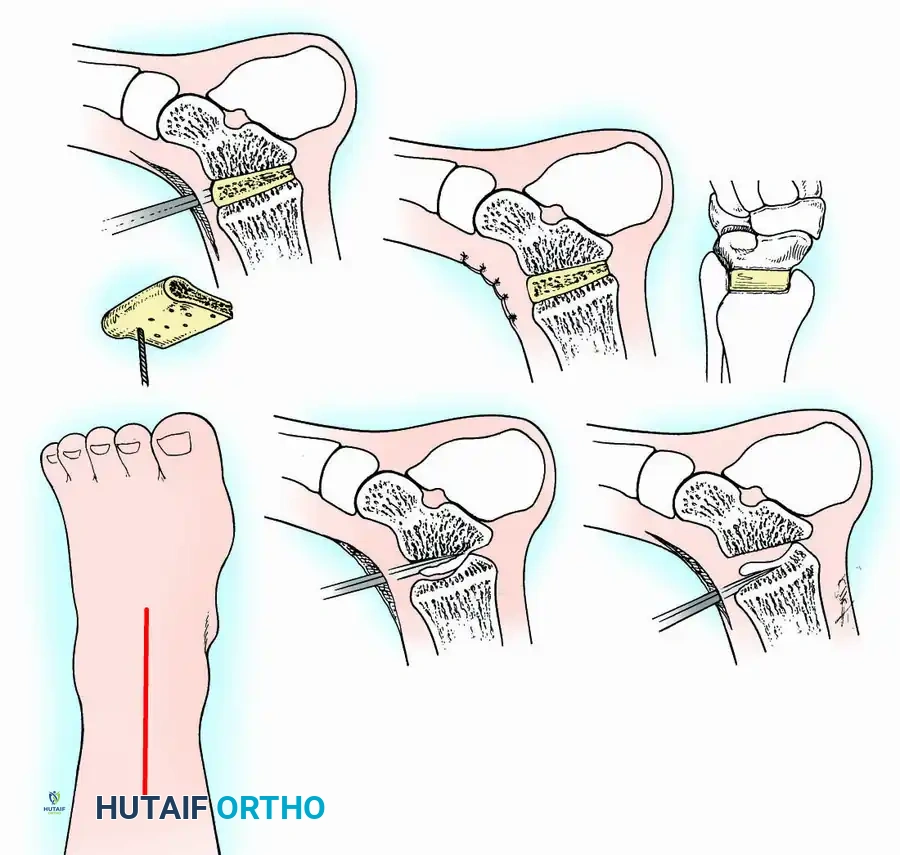

The anterior approach is typically performed through the internervous plane between the extensor hallucis longus (EHL) and the extensor digitorum longus (EDL), often utilizing the anterior tibial tendon sheath. This provides excellent, direct visualization of the central tibiotalar articulation and allows for easy posterior translation of the talus. However, access to the medial and lateral gutters is restricted, sometimes necessitating accessory incisions.

Transmalleolar (Transfibular) Approach

This approach utilizes a lateral incision over the distal fibula. A transfibular osteotomy is performed, reflecting the distal fibula distally or excising it entirely to be used as autograft. This provides unparalleled exposure of the lateral half of the joint and the posterior facet. It is highly effective for correcting severe varus/valgus deformities. A supplementary medial incision (medial malleolar osteotomy) can be added for complete joint exposure.

Preparation of Joint Surfaces

Two primary philosophies exist for joint preparation:

- Contour Preservation (Fishscaling): The remaining articular cartilage is meticulously denuded using curettes, and the subchondral bone is "fishscaled" or aggressively petalled with a sharp osteotome. This preserves the native ball-and-socket contour of the ankle, maximizing inherent bony stability and minimizing limb shortening.

- Planar Resection (Parallel Cuts): Two parallel cuts are made—one through the distal tibial plafond and one through the talar dome—using an oscillating saw. This technique resects a minimal amount of bone but creates perfectly flat, highly vascular cancellous surfaces that allow for excellent apposition and easy posterior translation of the talus. Extramedullary alignment guides (often repurposed from total knee arthroplasty systems) can be utilized to ensure precise, parallel resections.

Fixation Techniques

Fixation is achieved via external compression frames, large-diameter internal cancellous screws, or intramedullary devices. The choice of fixation depends heavily on bone quality, soft-tissue integrity, and the presence of infection.

Internal fixation is currently the preferred method for uncomplicated ankle arthrodesis due to higher union rates, superior patient comfort, and the elimination of pin-tract infections. Biomechanical studies demonstrate that crossed, large-diameter (6.5 mm or 7.3 mm) cannulated cancellous screws provide exceptional resistance to shear and torsional forces.

A standard construct involves two or three screws:

1. A "home run" screw directed from the posterior malleolus into the anterior neck of the talus.

2. A screw from the medial malleolus into the lateral body of the talus.

3. A screw from the anterolateral tibia into the medial talar body.